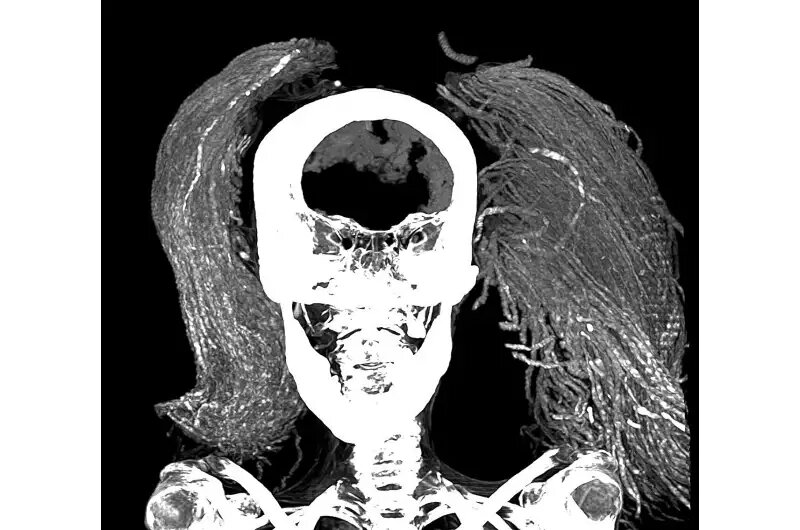

در پژوهش اخیر، سلیم از سیتیاسکن برای تشریح مجازی مومیایی و تخمین سن او، شناسایی آسیبشناسیها و وضعیت نگهداری او استفاده کرد. او و همکارش دکتر سامیه المرقانی از فنهای پیشرفتهای مانند میکروسکوپ الکترونی روبشی (SEM)، طیفسنجی تبدیل فوریه فروسرخ (FTIR) و آنالیز پراش اشعه ایکس (XRD) برای شناسایی مواد استفاده کردند.

سلیم از تصاویر CT دوبعدی و سهبعدی تخمین زد که قد زن در زمان زندگی 1.54 متر بوده است. بر اساس مورفولوژی مفصل بین دو استخوان لگن، که با افزایش سن صاف میشود، تصاویر سی تی تخمین زدند که او در زمان مرگ تقریباً 48 سال سن داشته است. او از آرتریت خفیف ستون فقرات رنج میبرد که از وجود استئوفیت ها یا خارهای استخوانی روی مهرهها مشهود بود.

همچنین هیچ برشی بر بدن مومیایی پیدا نشد و این بااینکه مغز، دیافراگم، قلب، ریهها، کبد، طحال، کلیهها و روده هنوز وجود دارند، مطابقت داشت. این تعجبآور بود، زیرا روش کلاسیک مومیایی در پادشاهی جدید (1550-1069 قبل از میلاد) شامل برداشتن همه این اندامها بهجز قلب بود.